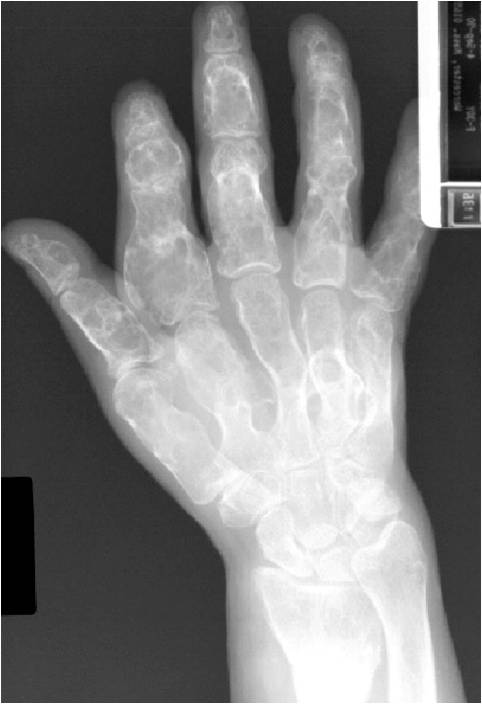

- 50% involve hands and feet (mostly phalanges)

- Localized, radiolucent defect usually with punctate calcifications

- Calcifications are stippled, punctate, popcorn like calcifications and “Ring and Arc” calcifications

- Cortex may be scalloped and thinned in the phalanges

- Geographic lytic lesion

- Expansile remodeling with thinned cortex

- Chondroid matrix with calcifications in majority of tumors

- Approximately 20% have limited or no calcifications